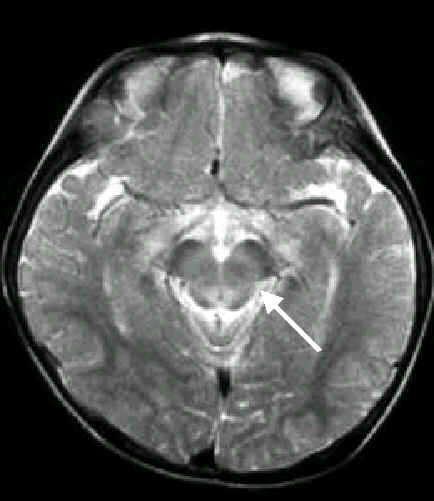

腦炎更往下

侵犯脊髓

腦炎侵犯

中腦的中央及橋腦、延腦的後面及小腦齒狀核,

更往下侵犯脊髓